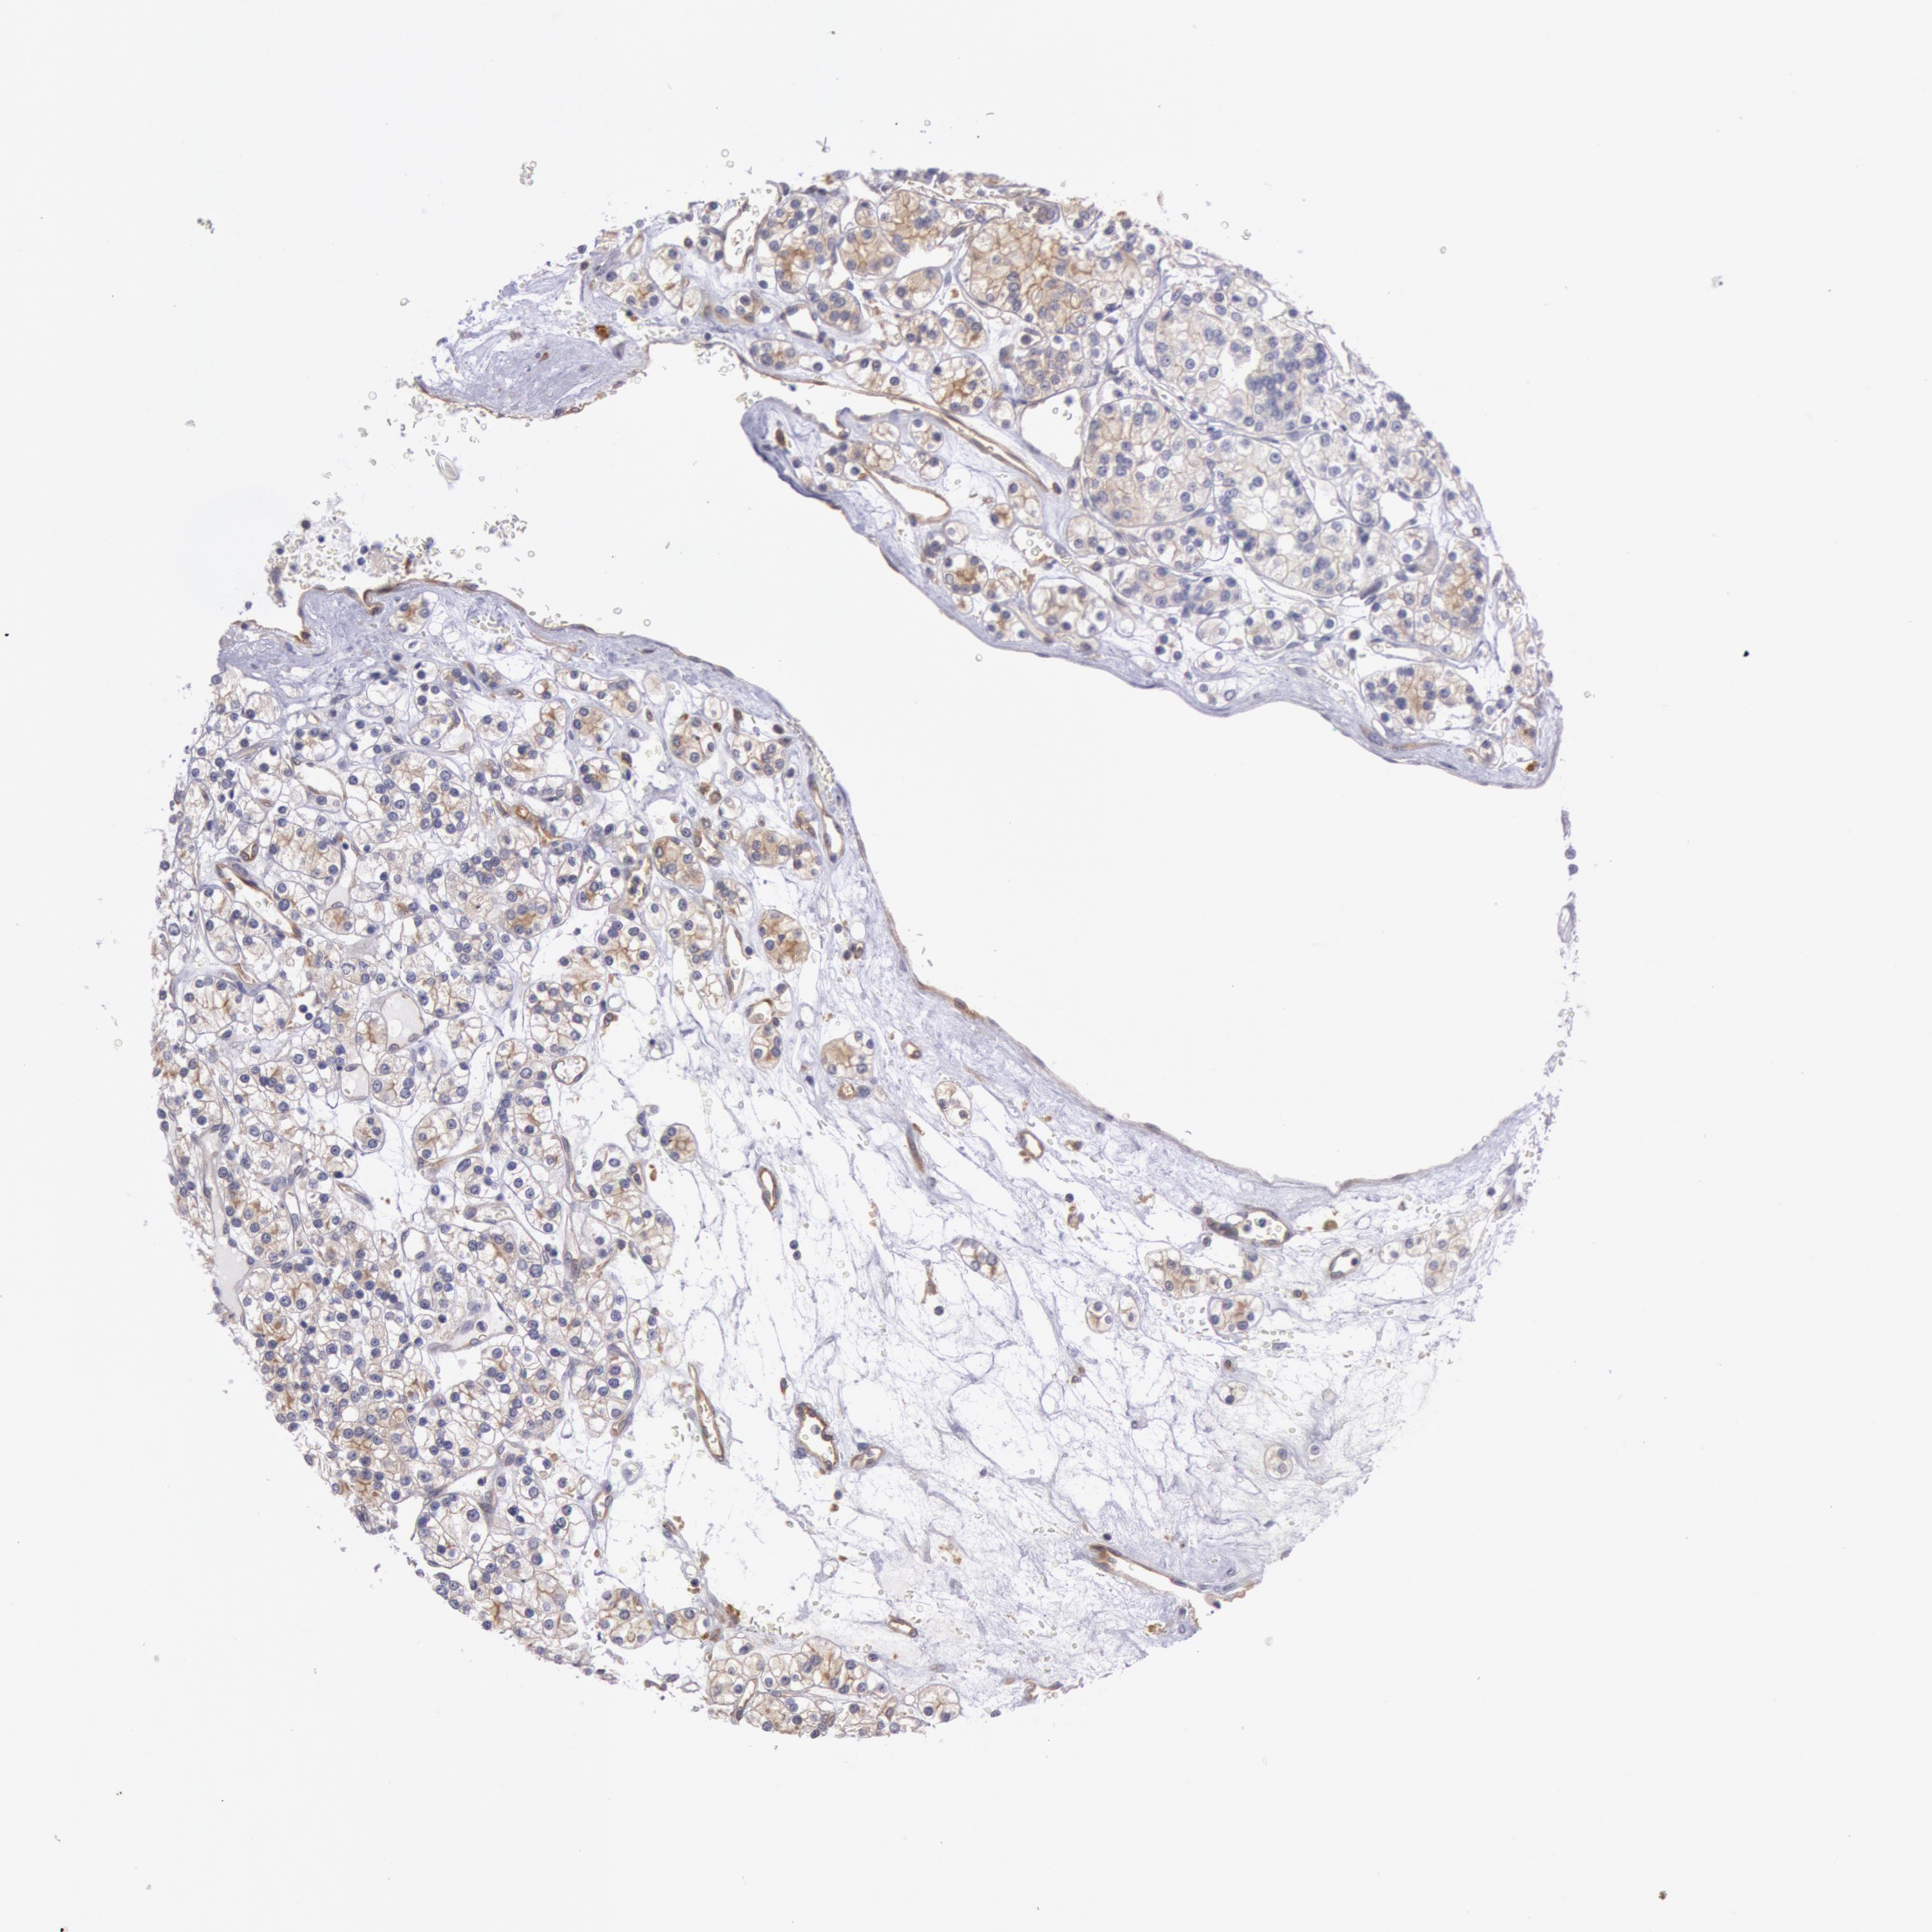

KIDNEY RENAL CLEAR CELL CARCINOMA (VALIDATION) - Interactive survival scatter ploti

The Survival Scatter plot shows the clinical status (i.e. dead or alive) for all individuals in the patient cohort, based on the same data that underlies the corresponding Kaplan-Meier plots. Patients that are alive at last time for follow-up are shown in blue and patients who have died during the study are shown in red.

MYO5A is not prognostic in Kidney Renal Clear Cell Carcinoma (validation)

: 9.49

Average pTPM 11.8

Number of samples 100